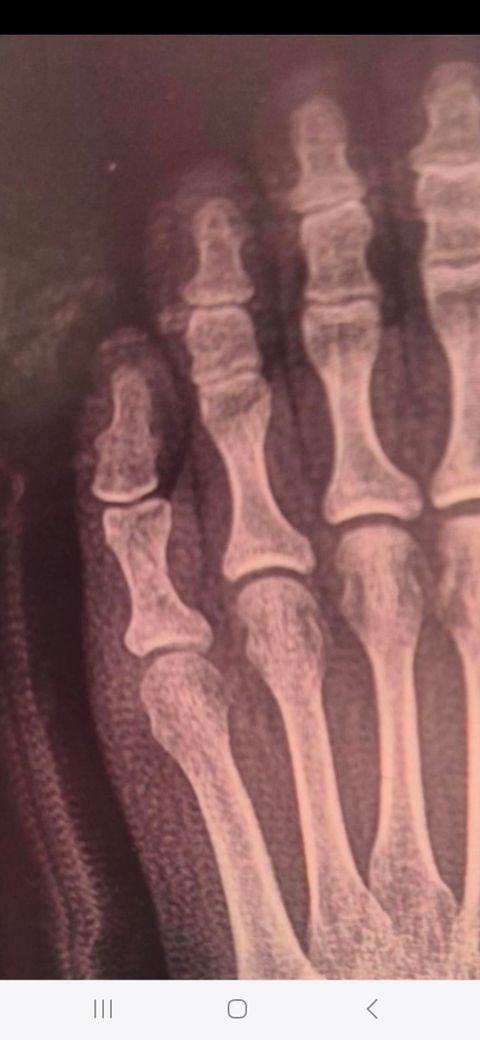

골절 2주차입니다 반깁스하다 이제 통깁스하고있어요. 엑스레이상 잘 붙고있는건지요? (1번은 2주전/ 2번은 현재 사진)

네 잘 회복 하는것으로 보입니다. 골절선은 남아있는걸로 보이는데 아직은 조심하는게 좋을듯 합니다.~

엑스레이상으로는 너무 잘붙고있는거같습니다!

보통은 모니터가 좋아야 확인이 가능한데, 이전에 비해 금이 간게 많이 사라진것을 육안으로 확인할 수 있는데요.

X-RAY 상으로는 잘 치유되고 있는 것으로 보입니다.

엑스레이상으로는 아직 완전히는 붙지않았지만 제자리로 잘 붙고있는 상황입니다 골절은 다시 심해질수있으니 항상 조심하셔서 관리하시길 바랍니다 깁스가끝난후에 보호대를 하시는것도 좋습니다